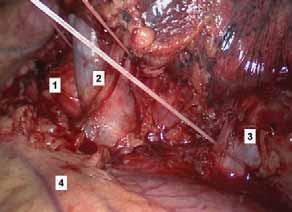

Rycina 70.5.

Rycina 70.6.